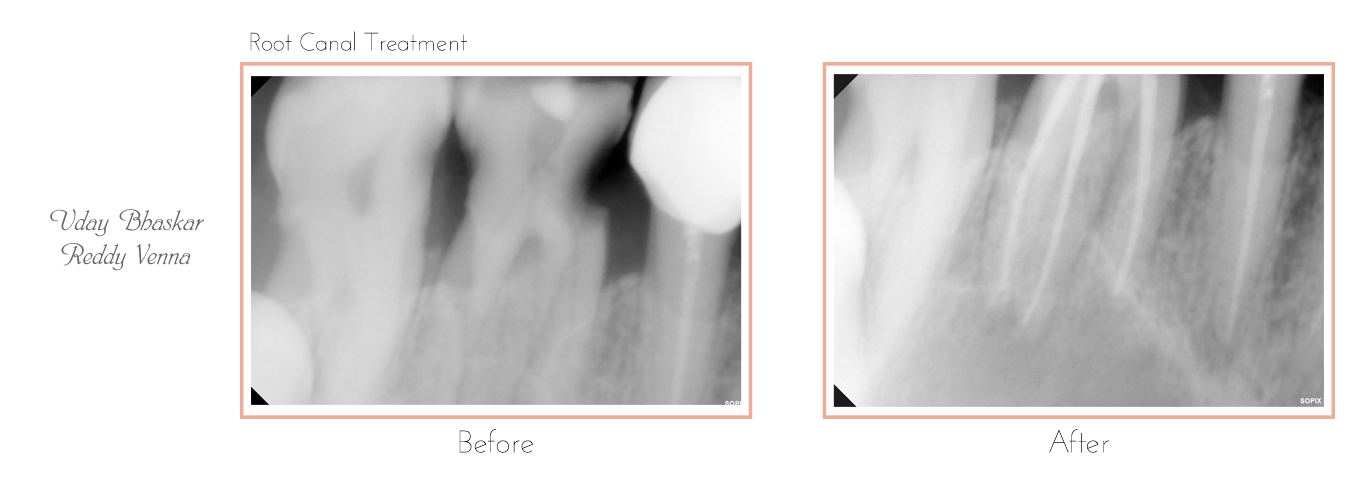

Root Canal Treatment

The very first step involves an X-ray which is taken to determine the extent and approach to infection. If required local anesthesia is administered before starting the treatment.

Clean and disinfected canals are then sealed and filled with an inert rubber-like filling material known as Gutta-Percha.